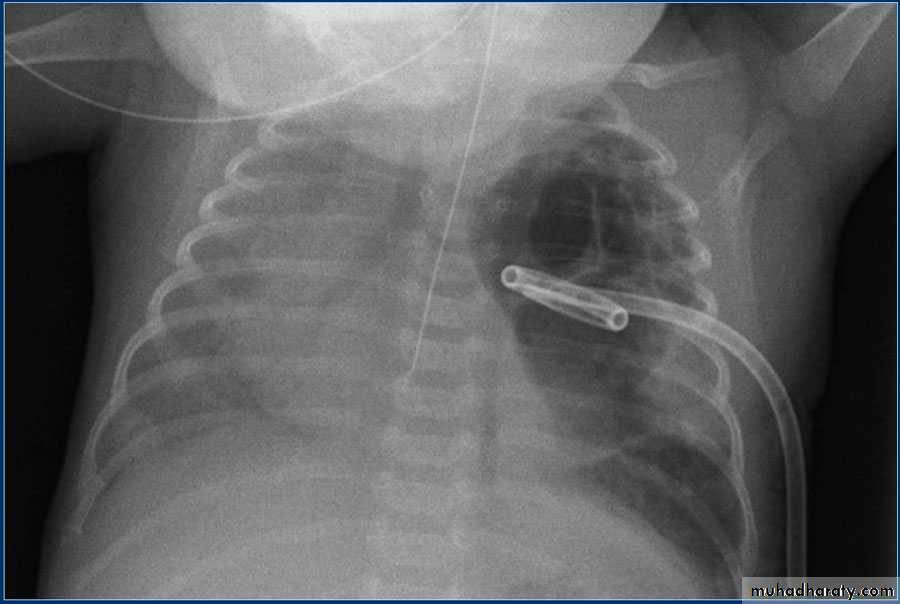

Fall from the 2nd floor